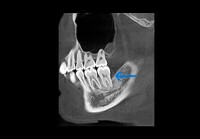

下の歯の奥側の骨が溶けてしまっています。

術前

レントゲン上で根っこの先端付近まで黒く抜けている部分が白くなっています。

骨が回復している様子が見られます。